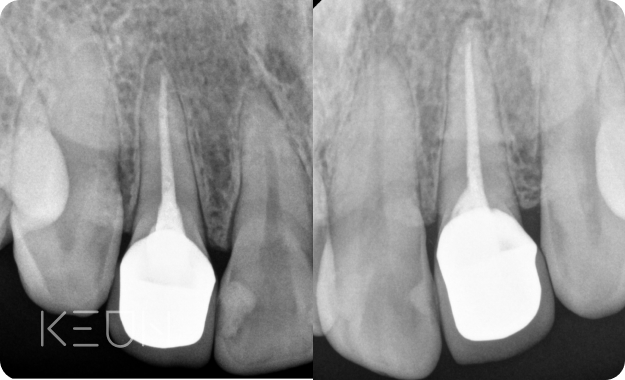

충치치료 전

CT를 촬영하는 이유.

눈에 잘 보이는 충치는 육안과 파노라마로도 충분히 진단이

가능하지만 치아 사이에 발생한 충치는 발견하기 어렵습니다.

3차원 CT를 통해 치아의 뿌리와 신경의 위치, 충치의 위치 등을

정확히 파악 후 치료할 수 있습니다.